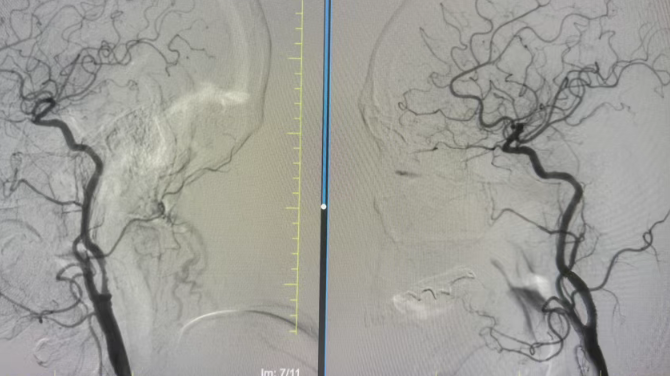

近日,国文医院神经介入团队凭借精湛的医术和专业的团队协作,成功为一名86岁高龄老人实施了颈动脉支架植入术,顺利打通堵塞的颈动脉,解除了脑卒中的致命风险,帮助老人重获健康,用实力守护了高龄患者的生命安全。

尽管方大爷年事已高,但手术的获益远大于风险。在医护团队详细告知病情、手术流程及风险后,方大爷及家属果断决定接受血管内介入治疗。完善术前准备后,手术在局部麻醉下顺利开展,介入团队凭借精湛的技术,精准定位血管狭窄部位,平稳将支架送入并成功释放,狭窄血管被顺利撑开,充沛的血流重新顺畅灌注大脑,为方大爷的生命中枢“续航”。